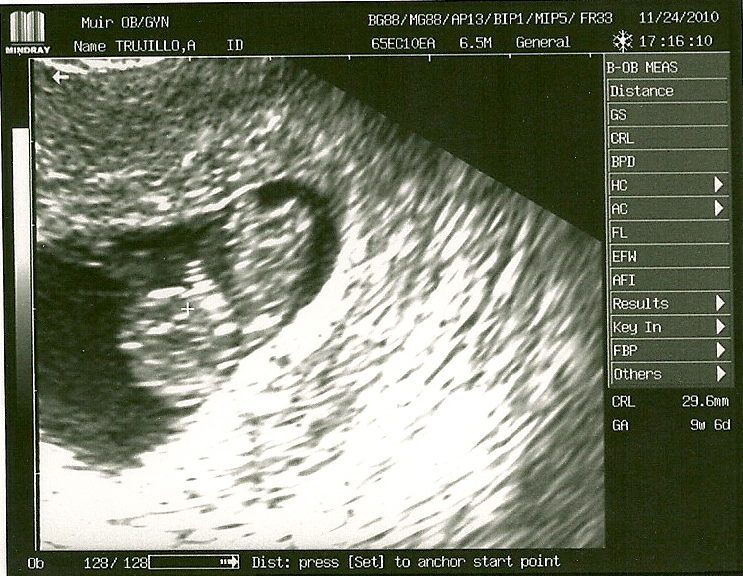

Aubrey's thoughts: I think it looks like me already! :)9 weeks, 4 days

We got to see our little one's heartbeat that day!  This is all starting to feel so real....12 weeks, 2 days